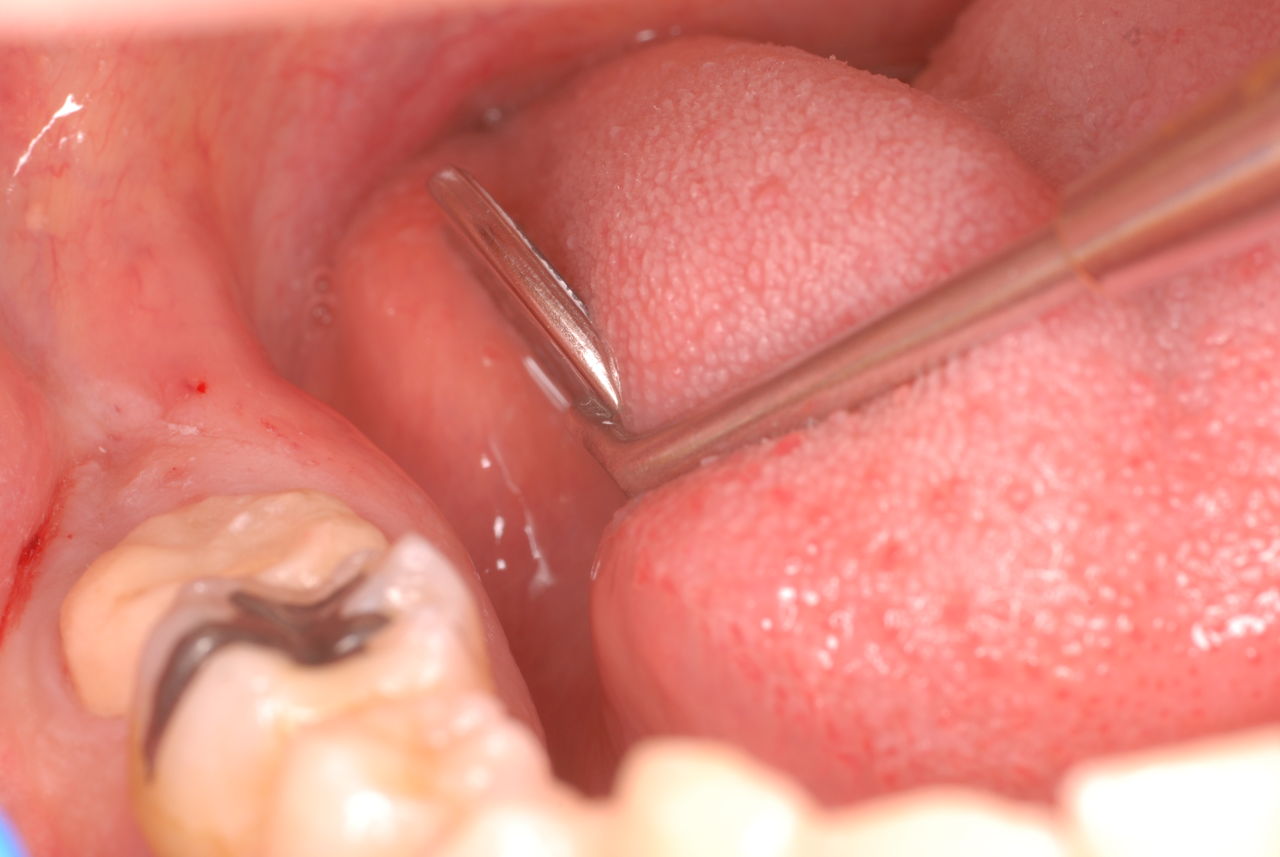

下記は患者に言われるままに血だらけでの不潔な状態で虫歯をとり埋めたようで全然適合していませんし、外れそうになっていました。

まずは掃除の仕方を学ぶべきだったのです。環境をある程度良くしてから治療しないのでほぼ失敗に終わり、またハズレて虫歯により崩壊してしまうのです。